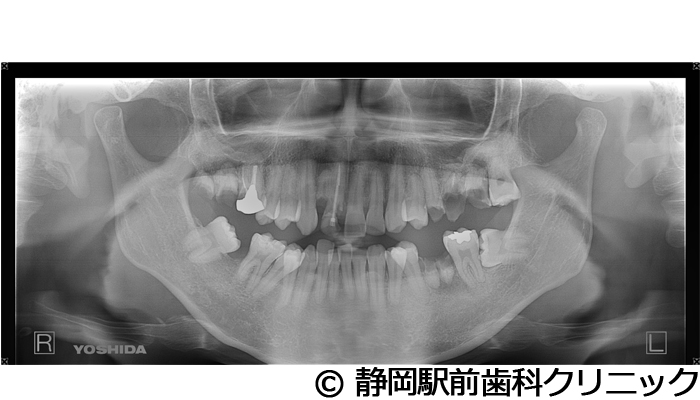

【症例5】全顎的インプラントとセラミックによる審美補綴

- 治療前

- 治療後

- 治療名

- 全顎的インプラントとセラミックによる審美補綴

- 費用

- 1,800,000円(税込)

- 期間

- 1年6ヵ月

治療内容

-

患者様の症状

全体的に歯がないため、噛めない。インプラント治療希望。

治療方法

全体的に残根は抜歯を行い、術前にCTを撮影し緻密に治療計画を立てた。インプラント埋入はブロックごとに行い、噛み合わせの調整を重ねた後、人工歯を被せて咬合と審美の回復を行いました。

治療結果

しっかり奥歯で食べ物を噛み切ることができるようになり、何でも食べることができるようになったと喜んでいただくことができました。口元を気にせずに笑うこともできるようになり、見た目もキレイになったとご満足いただけました。

※治療結果は個人差があります。

治療を行う上での注意点(リスク・副作用)

術後は、出血、腫れ、痛みなどが出る可能性があります。